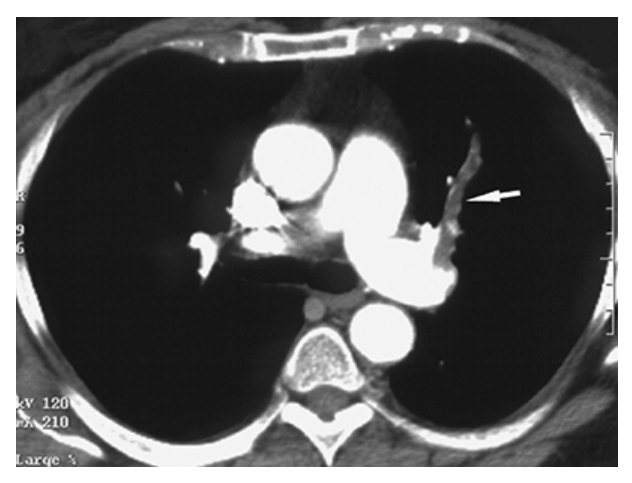

Atrial Myxoma. Contrast-enhanced axial CT shows a round filling defect/mass in the left atrium consistent with a myxoma (arrow).